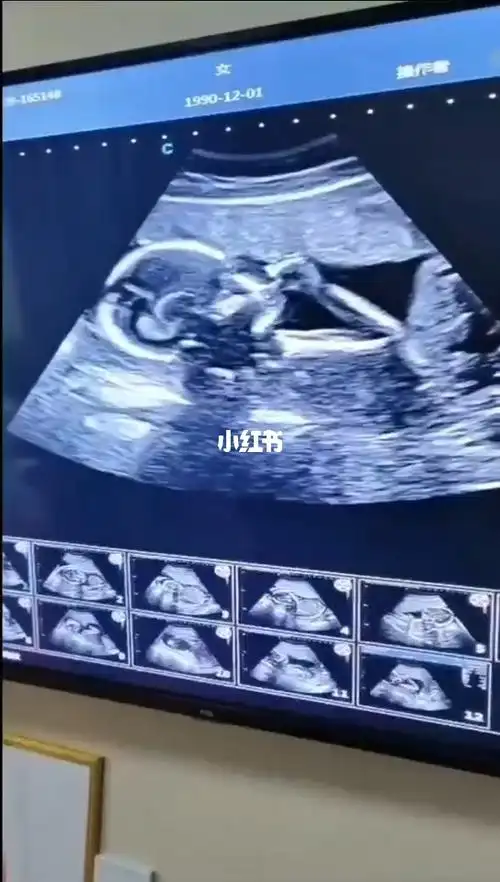

18周的胎宝宝吃手手好可爱呀